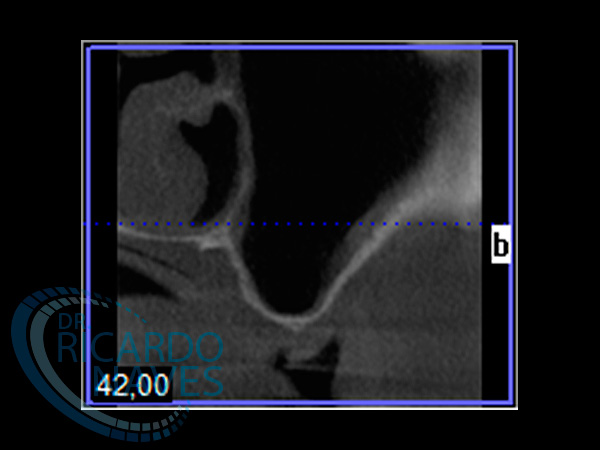

Obsérvese la gran atrofia a nivel de senos maxilares en donde seria imposible instalar implantes sin instalar injertos.

Tomografía post exodoncias con marcadores radio opacos en prótesis de trabajo.